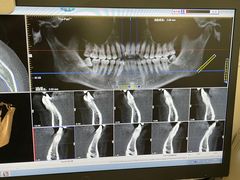

• 上海市第十人民医院(总院)

• -上海市第十人民医院(总院)

悟空 | 24-05-17